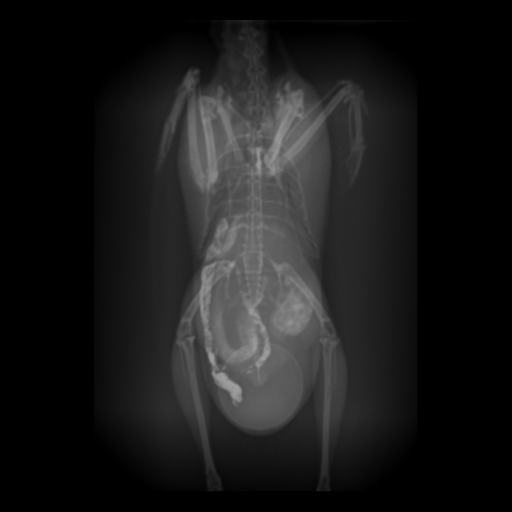

レントゲンを撮影したところ腹部下方に卵が確認できました。さらに卵巣や卵管の領域の陰影が拡大しており、筋胃が下方に押されている所見もあったため、超音波検査も実施しました。

手術はまず皮膚、腹筋、肝後中隔の順に切開し、一番手前にある卵の摘出から始めました。腹腔内を確認すると卵は卵管内にあることと、卵材か卵か疑われたところには殻の薄い軟卵があることがわかりました。よって2卵塞であることが判明しました。